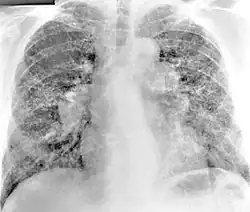

Chest radiography findings of berylliosis are non-specific. Early in the disease radiography findings are usually normal. In later stages interstitial fibrosis, pleural irregularities, hilar lymphadenopathy and ground-glass opacities have been reported.[19][20] Findings on CT are also not specific to berylliosis. Findings that are common in CT scans of people with berylliosis include parenchymal nodules in early stages. One study found that ground-glass opacities were more commonly seen on CT scan in berylliosis than in sarcoidosis. In later stages hilar lymphadenopathy, interstitial pulmonary fibrosis and pleural thickening.[20]